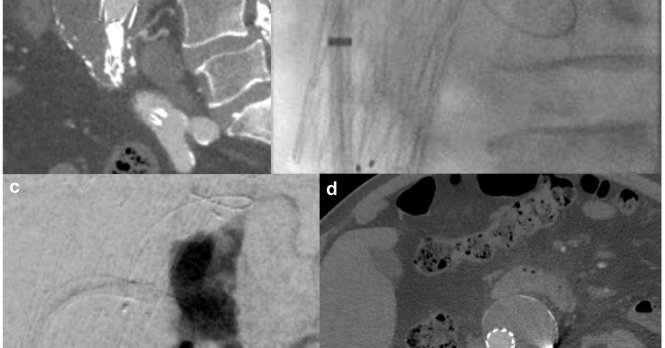

π©»β οΈ Rare trauma complication. This case highlights endovascular repair of a hepatic artery pseudoaneurysm with celiac dissection & intramural hematoma after blunt abdominal trauma, showing the power of minimally invasive management. π https://t.co/F9sOXcp1OU

Hepatic artery pseudoaneurysm is a concerning yet rare complication of blunt abdominal trauma, with treatment recommended upon diagnosis.1 Endovascular repair of hepatic artery aneurysms has gained...